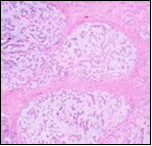

Multinodular tumour architecture is constituted by miniature, uniform, elliptical or spindle-shaped cells with scanty, eosinophilic, finely vacuolated cytoplasm and miniature, regular or hyperchromatic nuclei. Myxoid tumour matrix is envelops neoplastic cells configuring cords and strands. Nuclear pleomorphism is absent. Tiny foci of necrosis with focal chondroid differentiation may ensue6. Meningo-endothelial cells, physaliferous cells, rhabdoid cells, ductal differentiation and anaplastic cellular dedifferentiation is usually absent. Myoepithelial carcinoma displays nuclear atypia, elevated mitotic rate and extensive foci of tumour necrosis5. Figure 1, Figure 2, Figure 3, Figure 4, Figure 5, Figure 6, Figure 7, Figure 8.

Figure 1.Parachordoma on fine needle aspiration cytology depicting clusters of spheroidal cells with eosinophilic cytoplasm, regular nuclei and clumped, encompassing myxoid stroma 13.